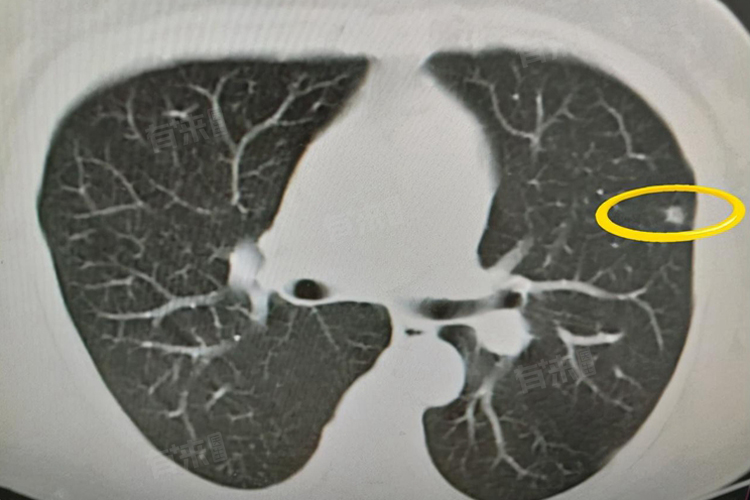

肺部毛玻璃结节6mm并不一定意味着情况严重,毛玻璃结节是指在胸部CT检查中表现为密度轻度增加,但其内的支气管血管束仍可显示的云雾状淡薄影。

- 但是也不能忽视其存在恶性的可能,虽然6mm的结节相对较小,但如果结节具有不良特征,如形态不规则、有分叶、毛刺征,或者结节内出现实性成分等,那么恶性的可能性会增加。一旦被证实为恶性,情况就较为严重,因为这意味着可能是早期肺癌。

还需要考虑结节的变化情况,对于6mm的肺部毛玻璃结节,医生通常会建议定期复查胸部CT,观察结节的大小、形态、密度等变化。如果在复查过程中,结节大小稳定,没有明显变化,那么良性的可能性较大。但如果结节逐渐增大,或者出现新的不良特征,如出现实性成分、结节边界变得更模糊等,那么恶性的风险就会上升,需要进一步评估和处理。